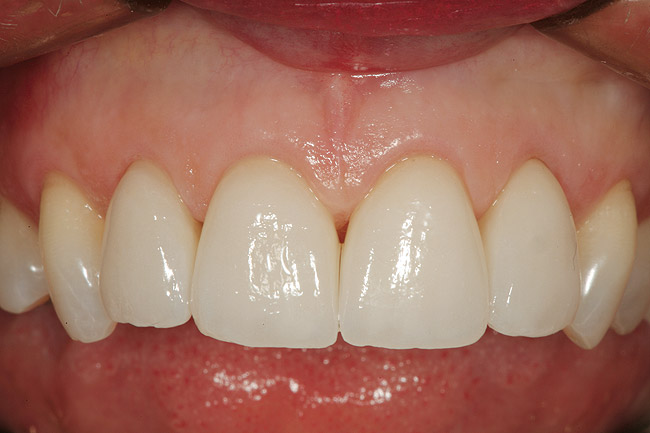

Figure 10  Facial view of the gingival tissues 9 weeks after open-flap surgery and at the time of placement of the ceramic restorations (original magnification 2x). Note the symmetrical positioning of the gingival zeniths of tooth Nos. 8 and 9. The level of tissue health 9 weeks after surgery is excellent.

Figure 10

Figure 11  The all-ceramic restorations (Venus‚Ñ¢ porcelain, Heraeus Kulzer, Inc, Armonk, NY) in place at the delivery appointment. (Ceramic artistry performed by Mr. Vincent Devaud, CFC, MDT, Pasadena, CA.)

Figure 11